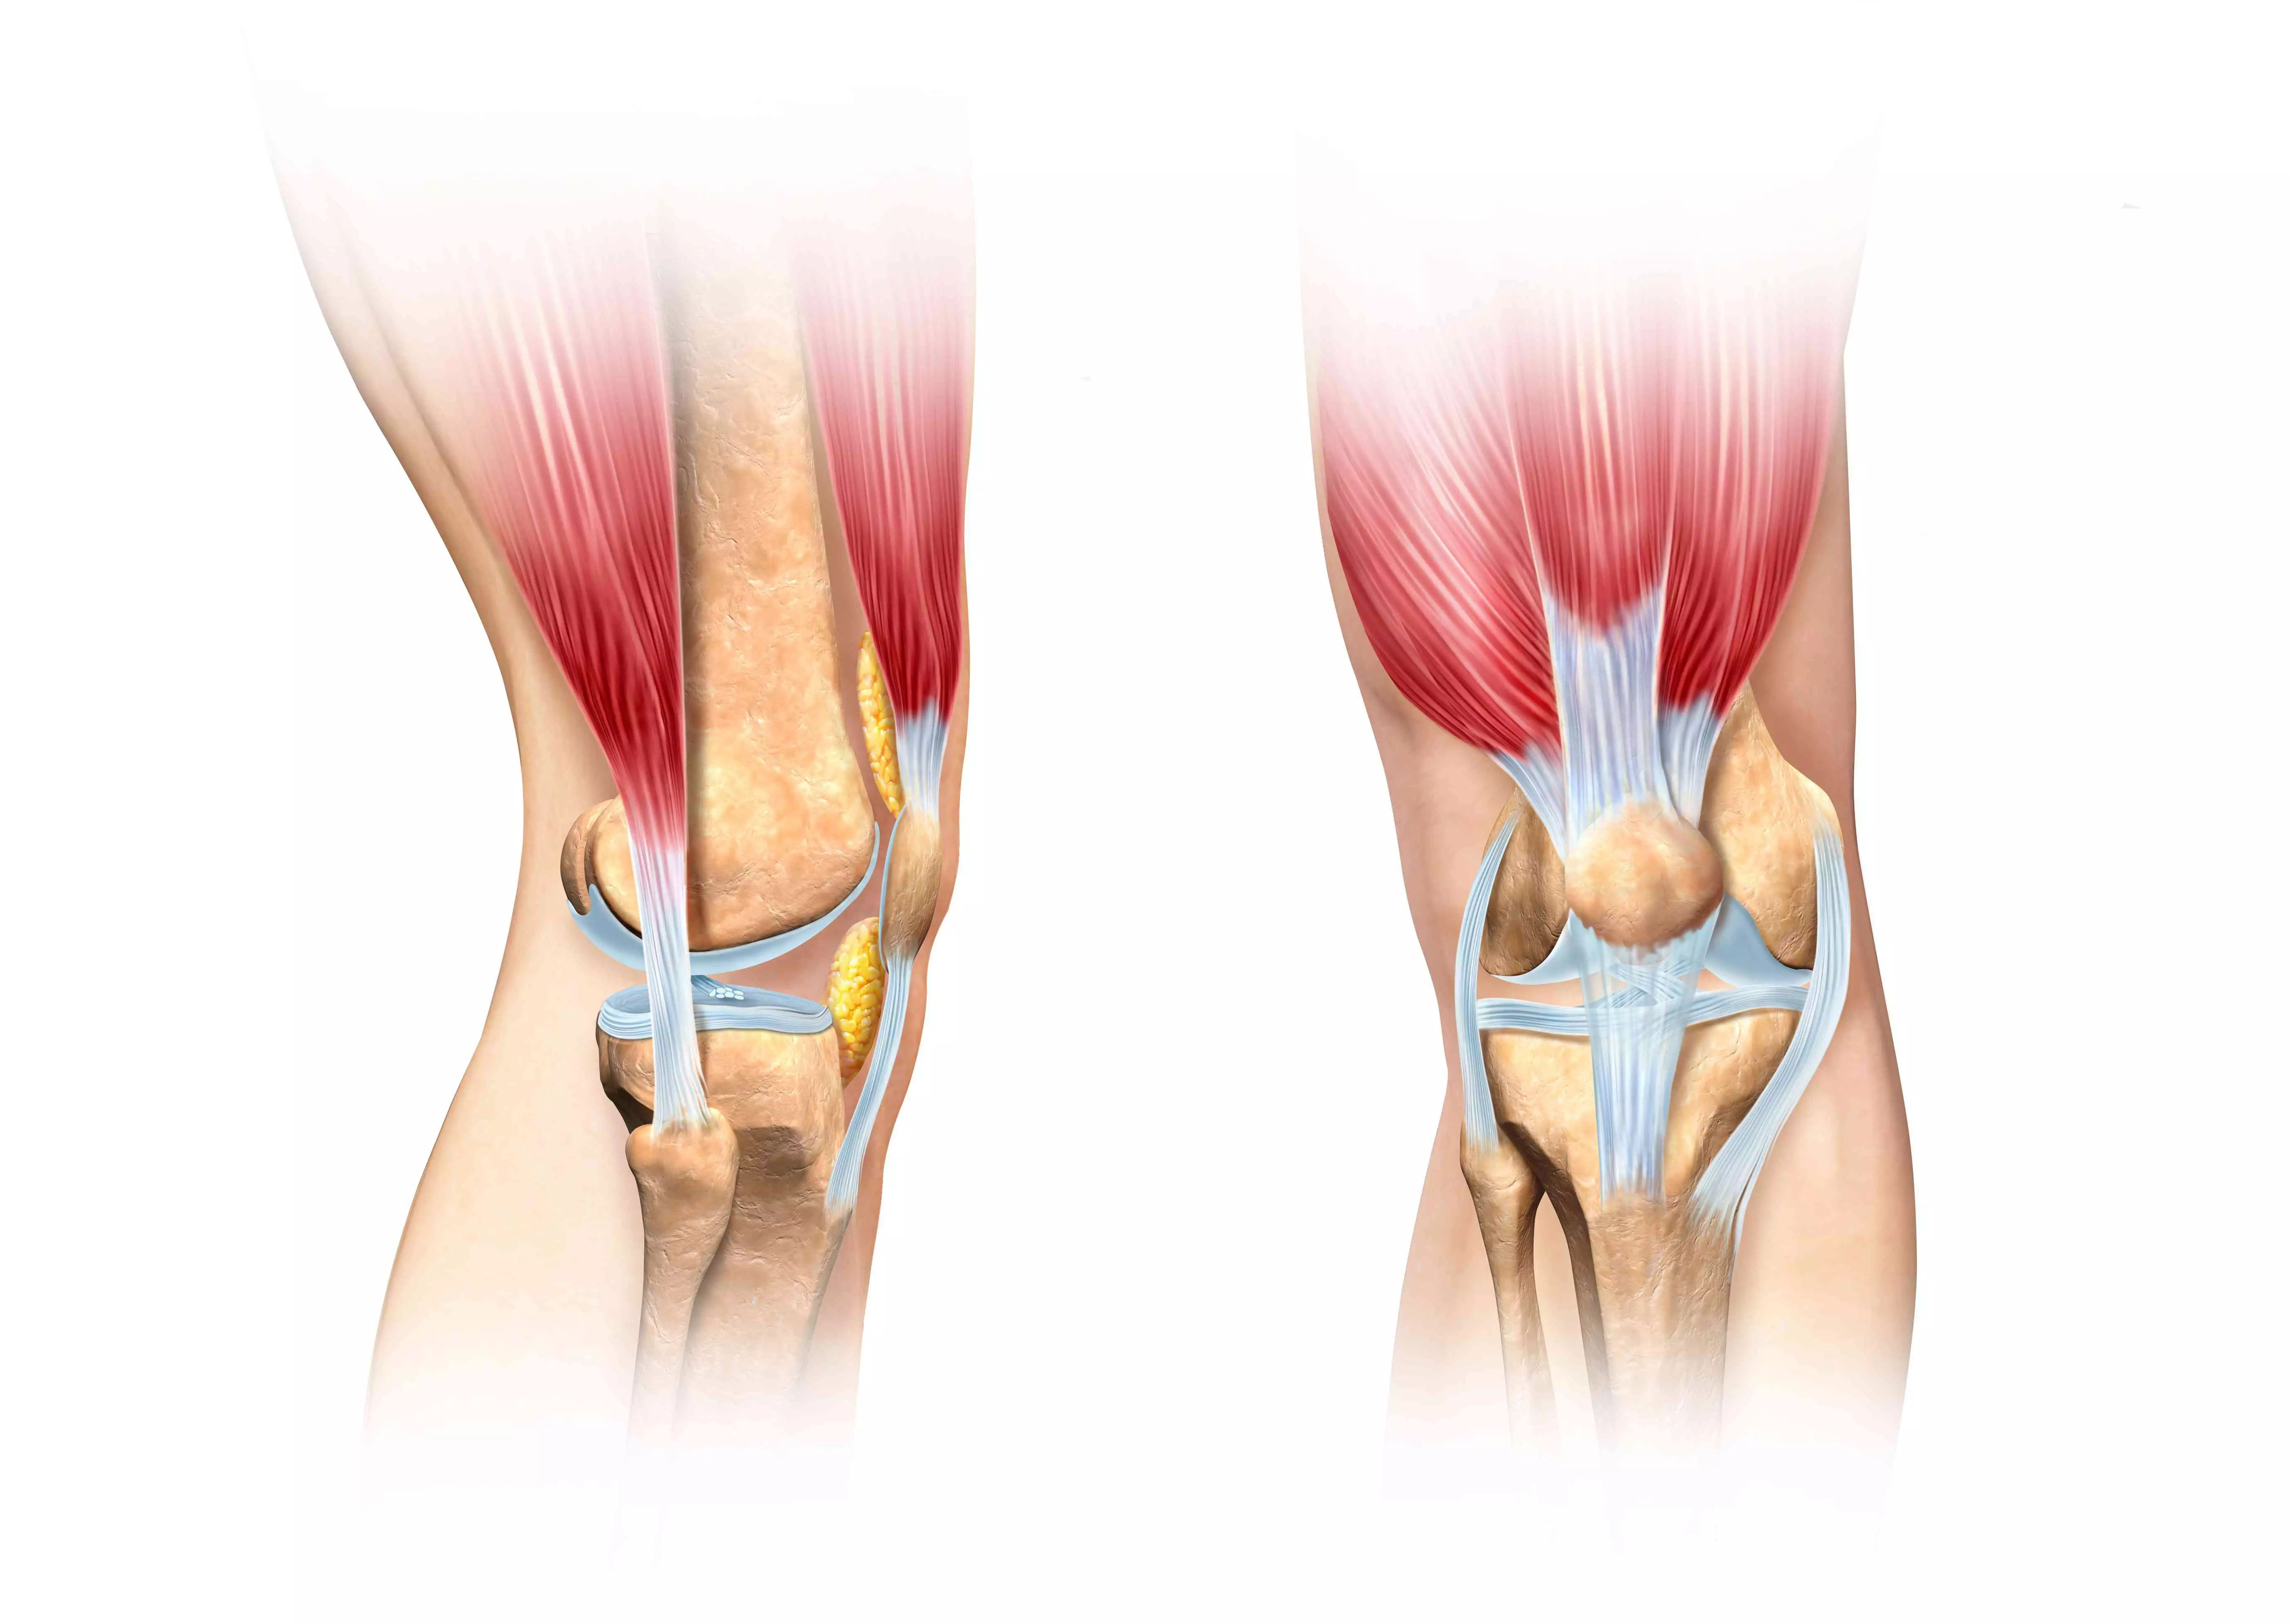

Проблемы с коленным суставом: флоттация и лечение